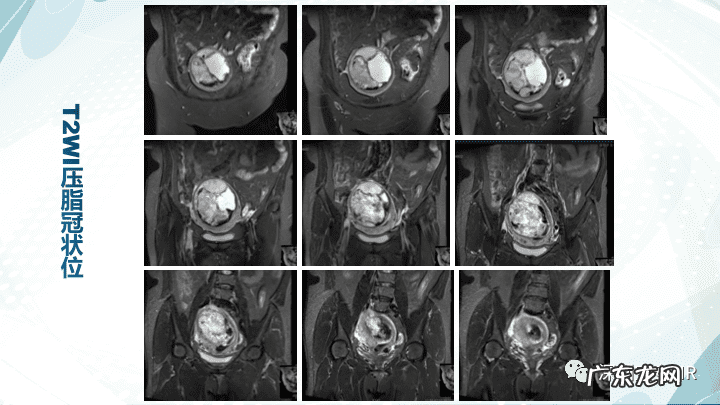

【子宫内膜间质肉瘤病理 子宫内膜间质肉瘤分期标准】下载放射沙龙app,获取更多影像科学习资料,更多学习视频等着你哦